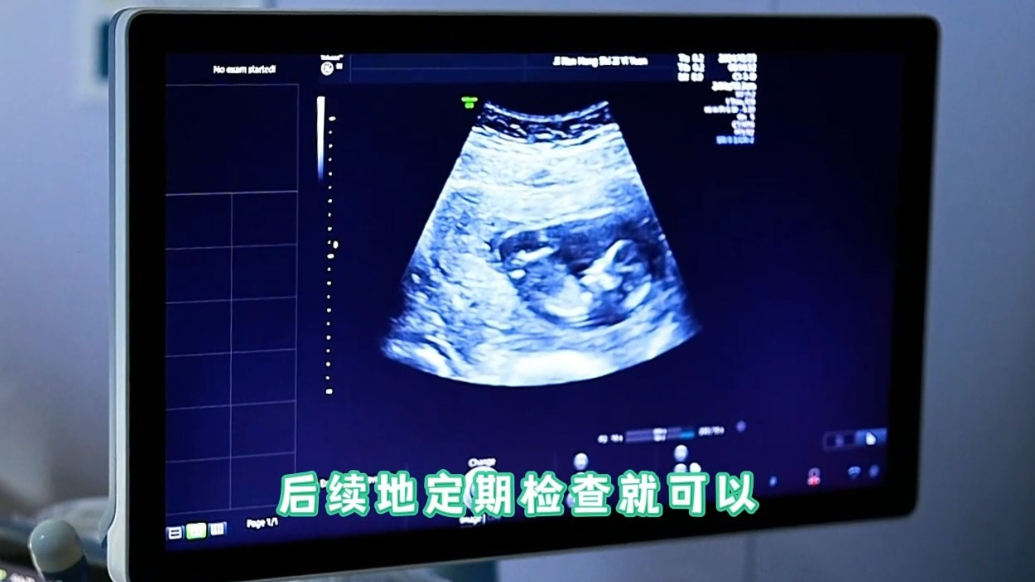

同样是停经、早孕反应,如何区分是正常怀孕还是危险的宫外孕? 今天,我们特别邀请了济南红绘医院邢爱君教授,来为大家讲解宫外孕的相关问题。